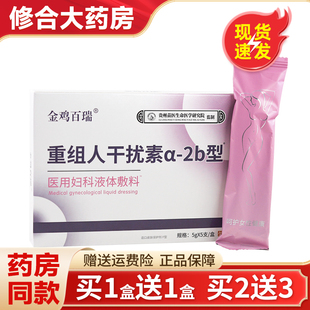

原价 15.9销量 0

¥15.9

修合大药房旗舰店